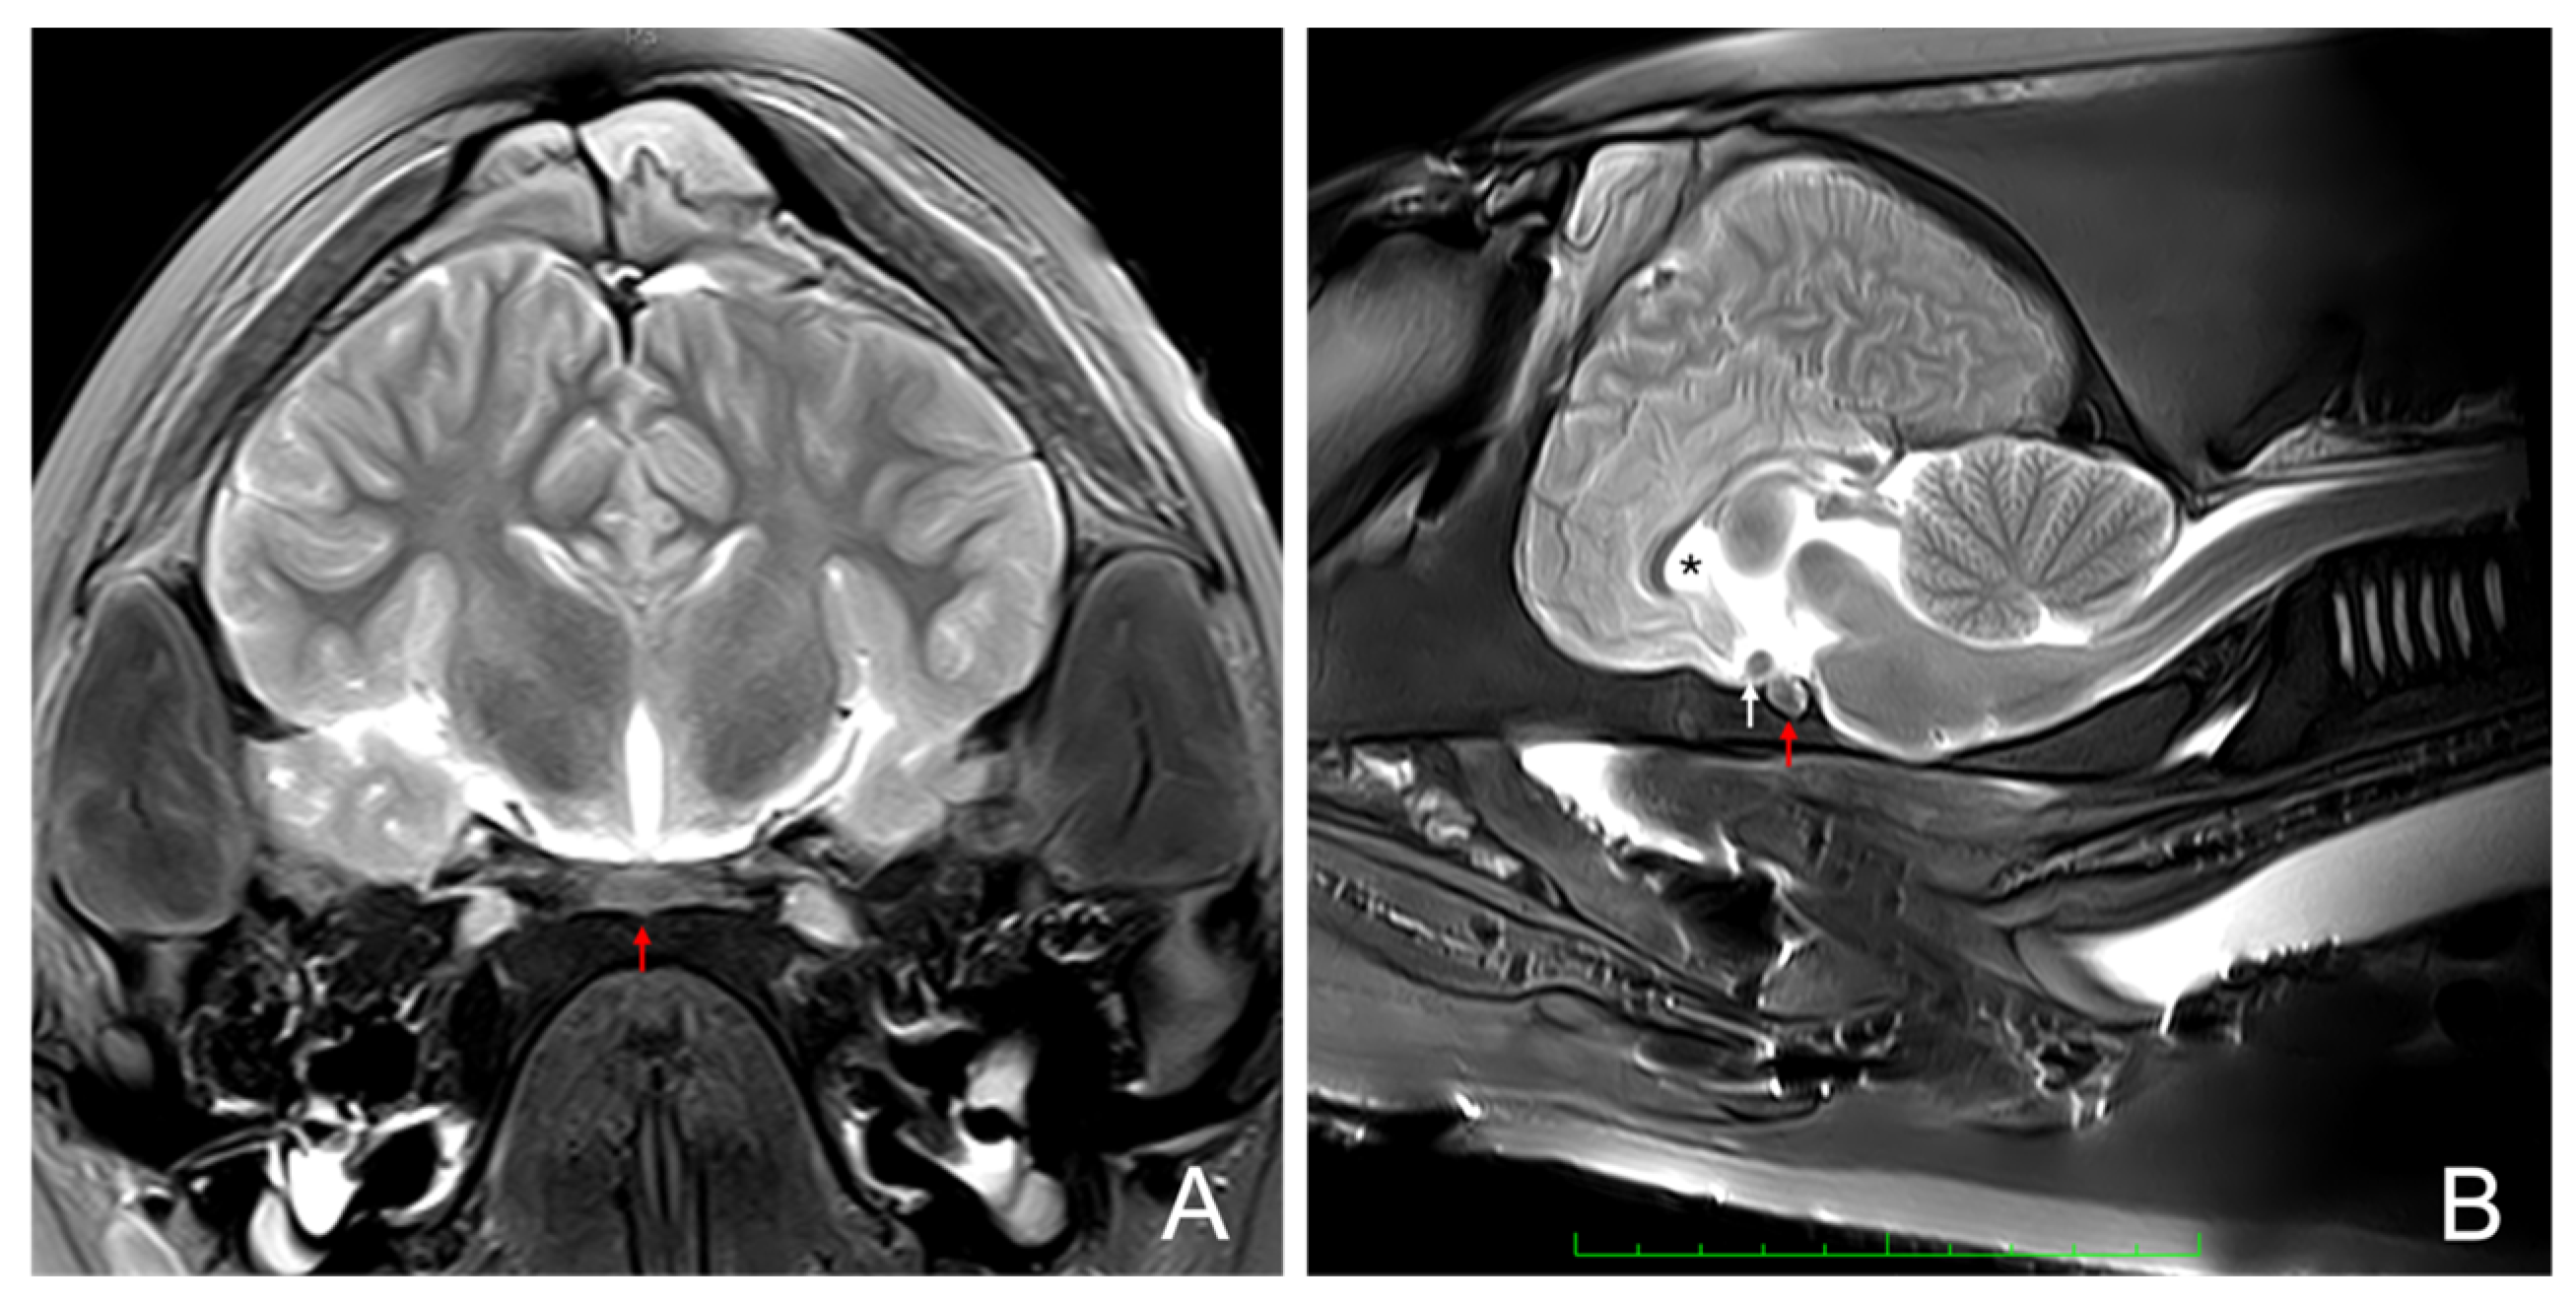

3.1. Magnetic Resonance Imaging

2.2. Anatomical Identification of the Pituitary Gland Using Magnetic Resonance Imaging (MRI)